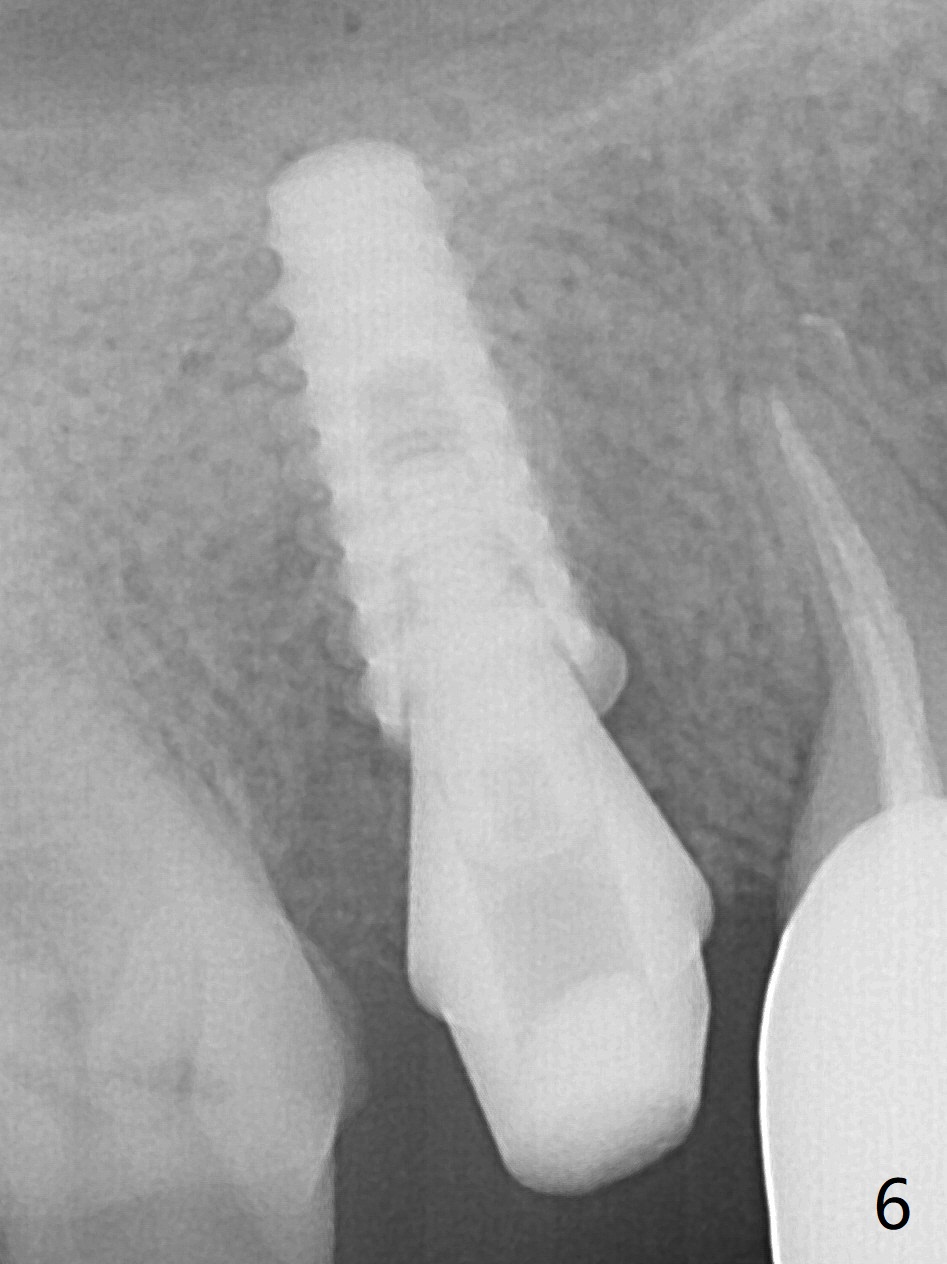

When the tooth #4 with vertical root fracture is extracted, the socket is large, approximately 6x10x10 mm (Fig.1 (mesiodistal x buccopalatal width x depth)). Osteotomy is established in the middle of the socket with 2 mm initial drill for 7 mm, 2.8 and 3.6 mm rounds drills (from DIO Sinus Master Kit) for < 7 mm, and 3.0 and 3.8 mm Magic Expanders. A 4x11 mm dummy implant is placed with insertion torque of 30 Ncm (Fig.2,3 (^: sinus floor)). There is a gap between the socket wall and the implant (*). To reduce the gap and periimplantitis, a 5x11 mm IBS implant is placed with insertion torque > 50 Ncm after further osteotomy using Magic Drills (Fig.4,5). Following placement of 5.5x4(4) mm abutment (A) and bone graft (data not shown), a splinted provisional is fabricated at #3 and 4. The provisional is stable 3 months postop (Fig.6,7). The peri-implant gaps (Fig.4,5) seem to disappear (Fig.6) with the help of bone graft. Bone graft appears to remain between the implant fins (Fig.7 arrows). Impression is taken 4.5 months postop (Fig.8,9). The abutment dislodges 4 months post cementation. After retightening, there is clearance for shim after use of 2 layers of thick articulating paper. Is the abutment screw too short? Or Titanium V is too hard for welding? The abutment/crown dislodges again 1 year 3 month post cementation; it appears that the fact that the implant is placed deep contributes to abutment screw loosening (Fig.10,11). An abutment screw will be buried inside the implant well 10 days post initial retightening.